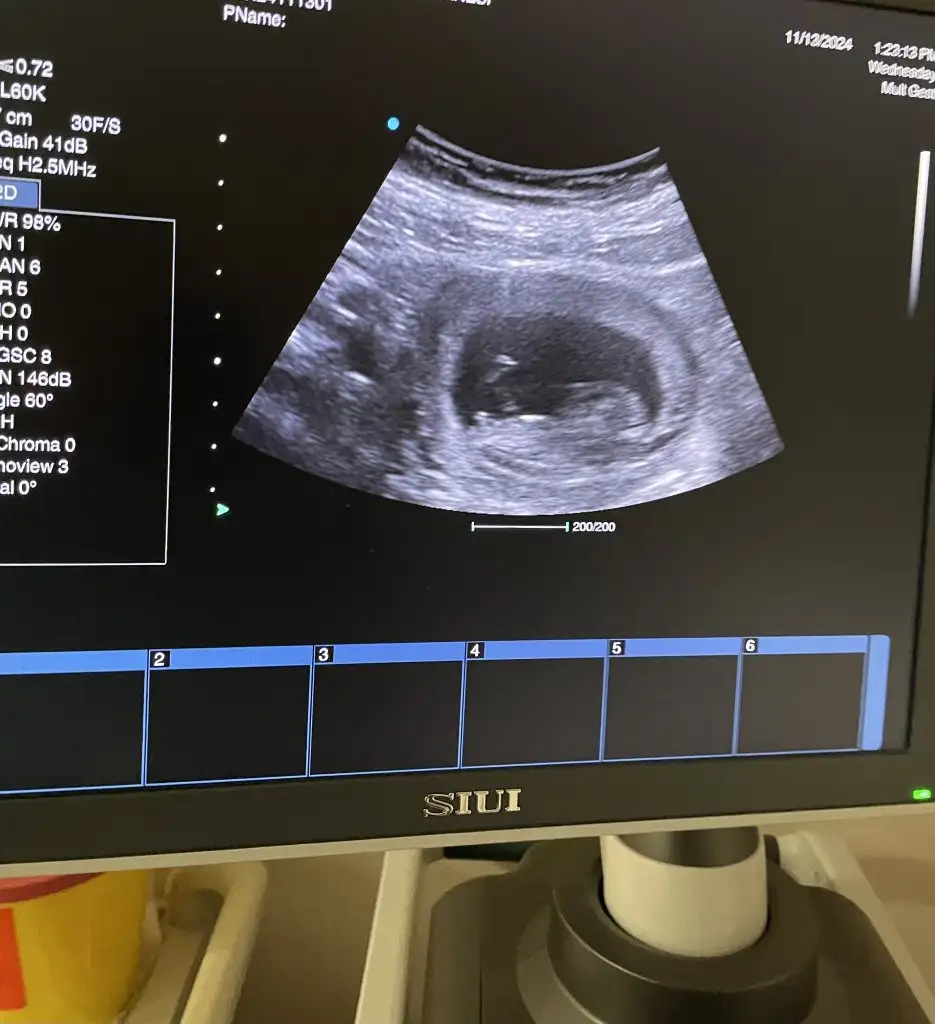

Kızlar yeni ultrason bu cinsiyet yorumu lütfen

• 61b6233d-55d3-4d1a-9ff5-c5eb16051583.webp

61b6233d-55d3-4d1a-9ff5-c5eb16051583.webp

31 KB · Görüntüleme: 53

Öncelikle hayırlı olsun. Nub için çok küçük . Ramzi teorisi içinse kız olabilir. Çok bildiğim bir şey değil 😊 hayırlısı olsun

Benimkine de bakar mısınız şuan 10 haftalık :) diğerinde de 5 haftalıktı

• image.webp

image.webp

30,3 KB · Görüntüleme: 41

• IMG_8888.webp

IMG_8888.webp

40,3 KB · Görüntüleme: 43